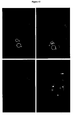

- Figure 10:

- Figure 12:

- Detection of a subcutaneous MEWO tumor in a mouse with AVE-PEG-RGD

Gd-liposomes after intravenous injection of the liposomal

formulation. The images on the left side were taken before the injection.

The two images on the right side were taken 20 minutes after the

injection. The upper and the lower images show two different sections

of the same mouse. Both circle 1 and

circle 2 in the upper images are located within the subcutaneous MEWO tumor. The subpopulation of tumor cells incircle 2 will also accumulate AVE-PEG-RGD Gd-liposomes after 1 h (Figure not shown). The white region in the lower right image lies within the MEWO tumor.